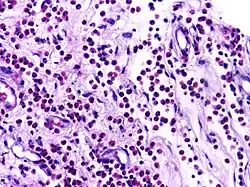

![]() |

Diffuse B-cell lymphoma | Lymph node FNA specimen showing diffuse large B cell lymphoma. | Category: Histopathology of diffuse large B cell lymphoma | Diffuse large B-cell lymphoma |